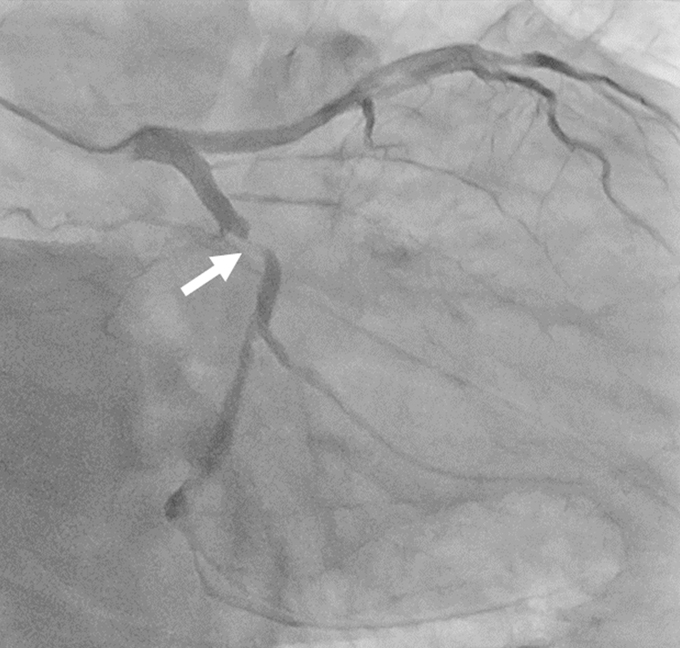

- junkankinaika-img02-20200229